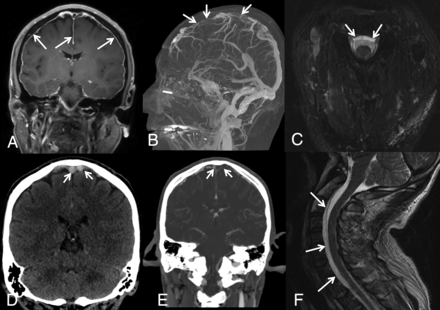

While cerebral venous sinus thrombosis affects only about 4 per 1 million people in the general population, the prevalence is about 2% in patients with SIH.62⇓⇓-65 There are several reasons why cerebral venous sinus thrombosis may be more prevalent in this population. As the volume of intracranial CSF decreases, compensation by the arterial and venous compartments must occur. Since veins are much more distensible than arteries, venous engorgement is common.66,67 Blood flows more slowly through veins of larger diameter, and this stasis increases coagulability.68 Furthermore, the characteristic brain sag of SIH can put tension on venous outflow tracts, thereby worsening venous expansion.62,67 In combination, these changes can provide an environment for thrombus formation within the venous sinuses (Fig 6). In patients with SIH, superimposed cerebral venous sinus thrombosis should be considered when there is a change in headache quality (from predictable and positional to severe and unrelenting) or new neurologic deficits develop.62,67,69⇓⇓-72 Similarly, patients with unprovoked cerebral venous sinus thrombosis should be assessed for possible underlying SIH.

SIH presenting with venous sinus thrombosis. A 43-year-old man presented with sudden onset of headaches, dizziness, and nausea clinically suspected to represent migraines. A, Contrast-enhanced T1-weighted image demonstrates diffuse, smooth, nonspecific thin pachymeningeal enhancement (arrows). The patient presented to the emergency department 3 days later with a marked increase in his headache and sudden onset of right lower-extremity weakness. D, Unenhanced coronal head CT demonstrates high attenuation and expansile content within the superior sagittal sinus and adjacent cortical veins, compatible with acute dural venous sinus and cortical vein thrombosis (selected clot highlighted by arrows). Sagittal MIP (B) and coronal (E) images from a contrast-enhanced CT venogram confirm a long-segment acute, expansile thrombus as a filling defect within the superior sagittal sinus, as well as multiple bilateral left-greater-than-right superior cortical veins (arrows). While he was being treated for sinus thrombosis, he reported that his headaches were orthostatic in nature. His condition continued to deteriorate with progression of the thrombosis despite treatment and parenchymal hemorrhage. Axial (C) and sagittal (F) T2WI demonstrates a ventral extradural fluid collection. A hyperdynamic CT myelogram was performed, and a leak was found at a spiculated osteophyte at T1-2.